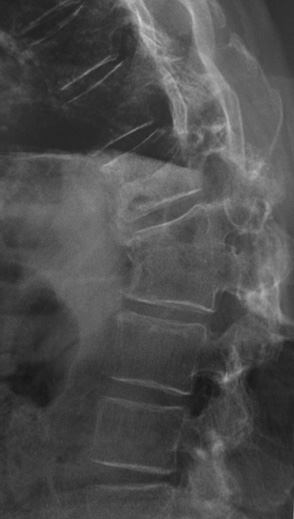

Un traitement est rapidement entrepris mais des douleurs lombo-radiculalgiques sévères font réaliser

Vous suivez un homme né en 1946 mesurant 1,92 m et pesant 87 kg ; ancien professeur d’éducation physique.

Il présente une ostéoporose sévère avec une perte de taille de 6 cm (il mesurait 1,98 m à 20 ans), un T score du rachis à – 3,5 DS et du total col à – 3 DS il y a 3 ans. Il présentait également une fracture de T12 de grade 3 de Génant depuis cette date. Tout le bilan était normal et vous avez débuté un traitement par bisphosphonate.

Il vient récemment vous consulter car il a été agressé devant son immeuble et il a été propulsé au sol. Il a ressenti des rachialgies intenses et